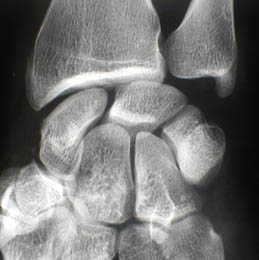

A - Radiographie de face du poignet (patient A) : Pas de facette articulaire pour l'hamatum au niveau du lunatum. Les 2 os sont nettement séparés. Viegas 1

B - Radiographie de face du poignet (patient B) : L'os crochu, hamatum, présente une surface articulaire avec le semi-lunaire (lunatum). Cette forme anatomique prédispose à la chondrite de l'hamatum. Viegas 2

Les deux configurations médiocarpiennes selon Viegas.